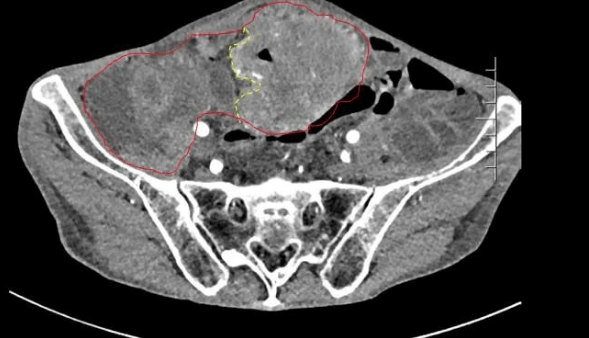

患者王大爷,男,72岁,发现腹腔肿物10余年,近两年来患者双下肢乏力、贫血,依靠间断输血维持着正常生活,出现头昏,行动困难,腹部疼痛及便血慕名来我院就诊。入院后查体评估患者年龄大,体质差,严重贫血,肺部感染及肠梗阻征象,腹部增强CT检查提示腹膜后巨大肿瘤,长径超过30厘米,占据大部分腹腔,并可能存在双原发肿瘤。

苗满园肿瘤外科团队在麻醉科/手术室的紧密配合下为该患者进行手术,术中发现肿瘤巨大,几乎占据了整个腹腔,从左侧向右腹腔延伸,向上将肝、肾挤向膈下,向左将胃及小肠挤向左上腹,向下深达盆腔内,包绕下腔静脉、肠系膜上动脉等大血管及输尿管,回盲部及回肠也受侵犯。手术难度巨大,风险极高。团队凭借着高超的手术技能和精准的手术预案沉着应对,迎难而上,应用高频电刀、超声刀、切割缝合器等先进设备,耗时近5小时为患者切除了巨大腹腔肿瘤,并联合右半结肠切除,术中出血仅50ml。术后病理为腹膜后巨大平滑肌瘤+回肠腺癌。